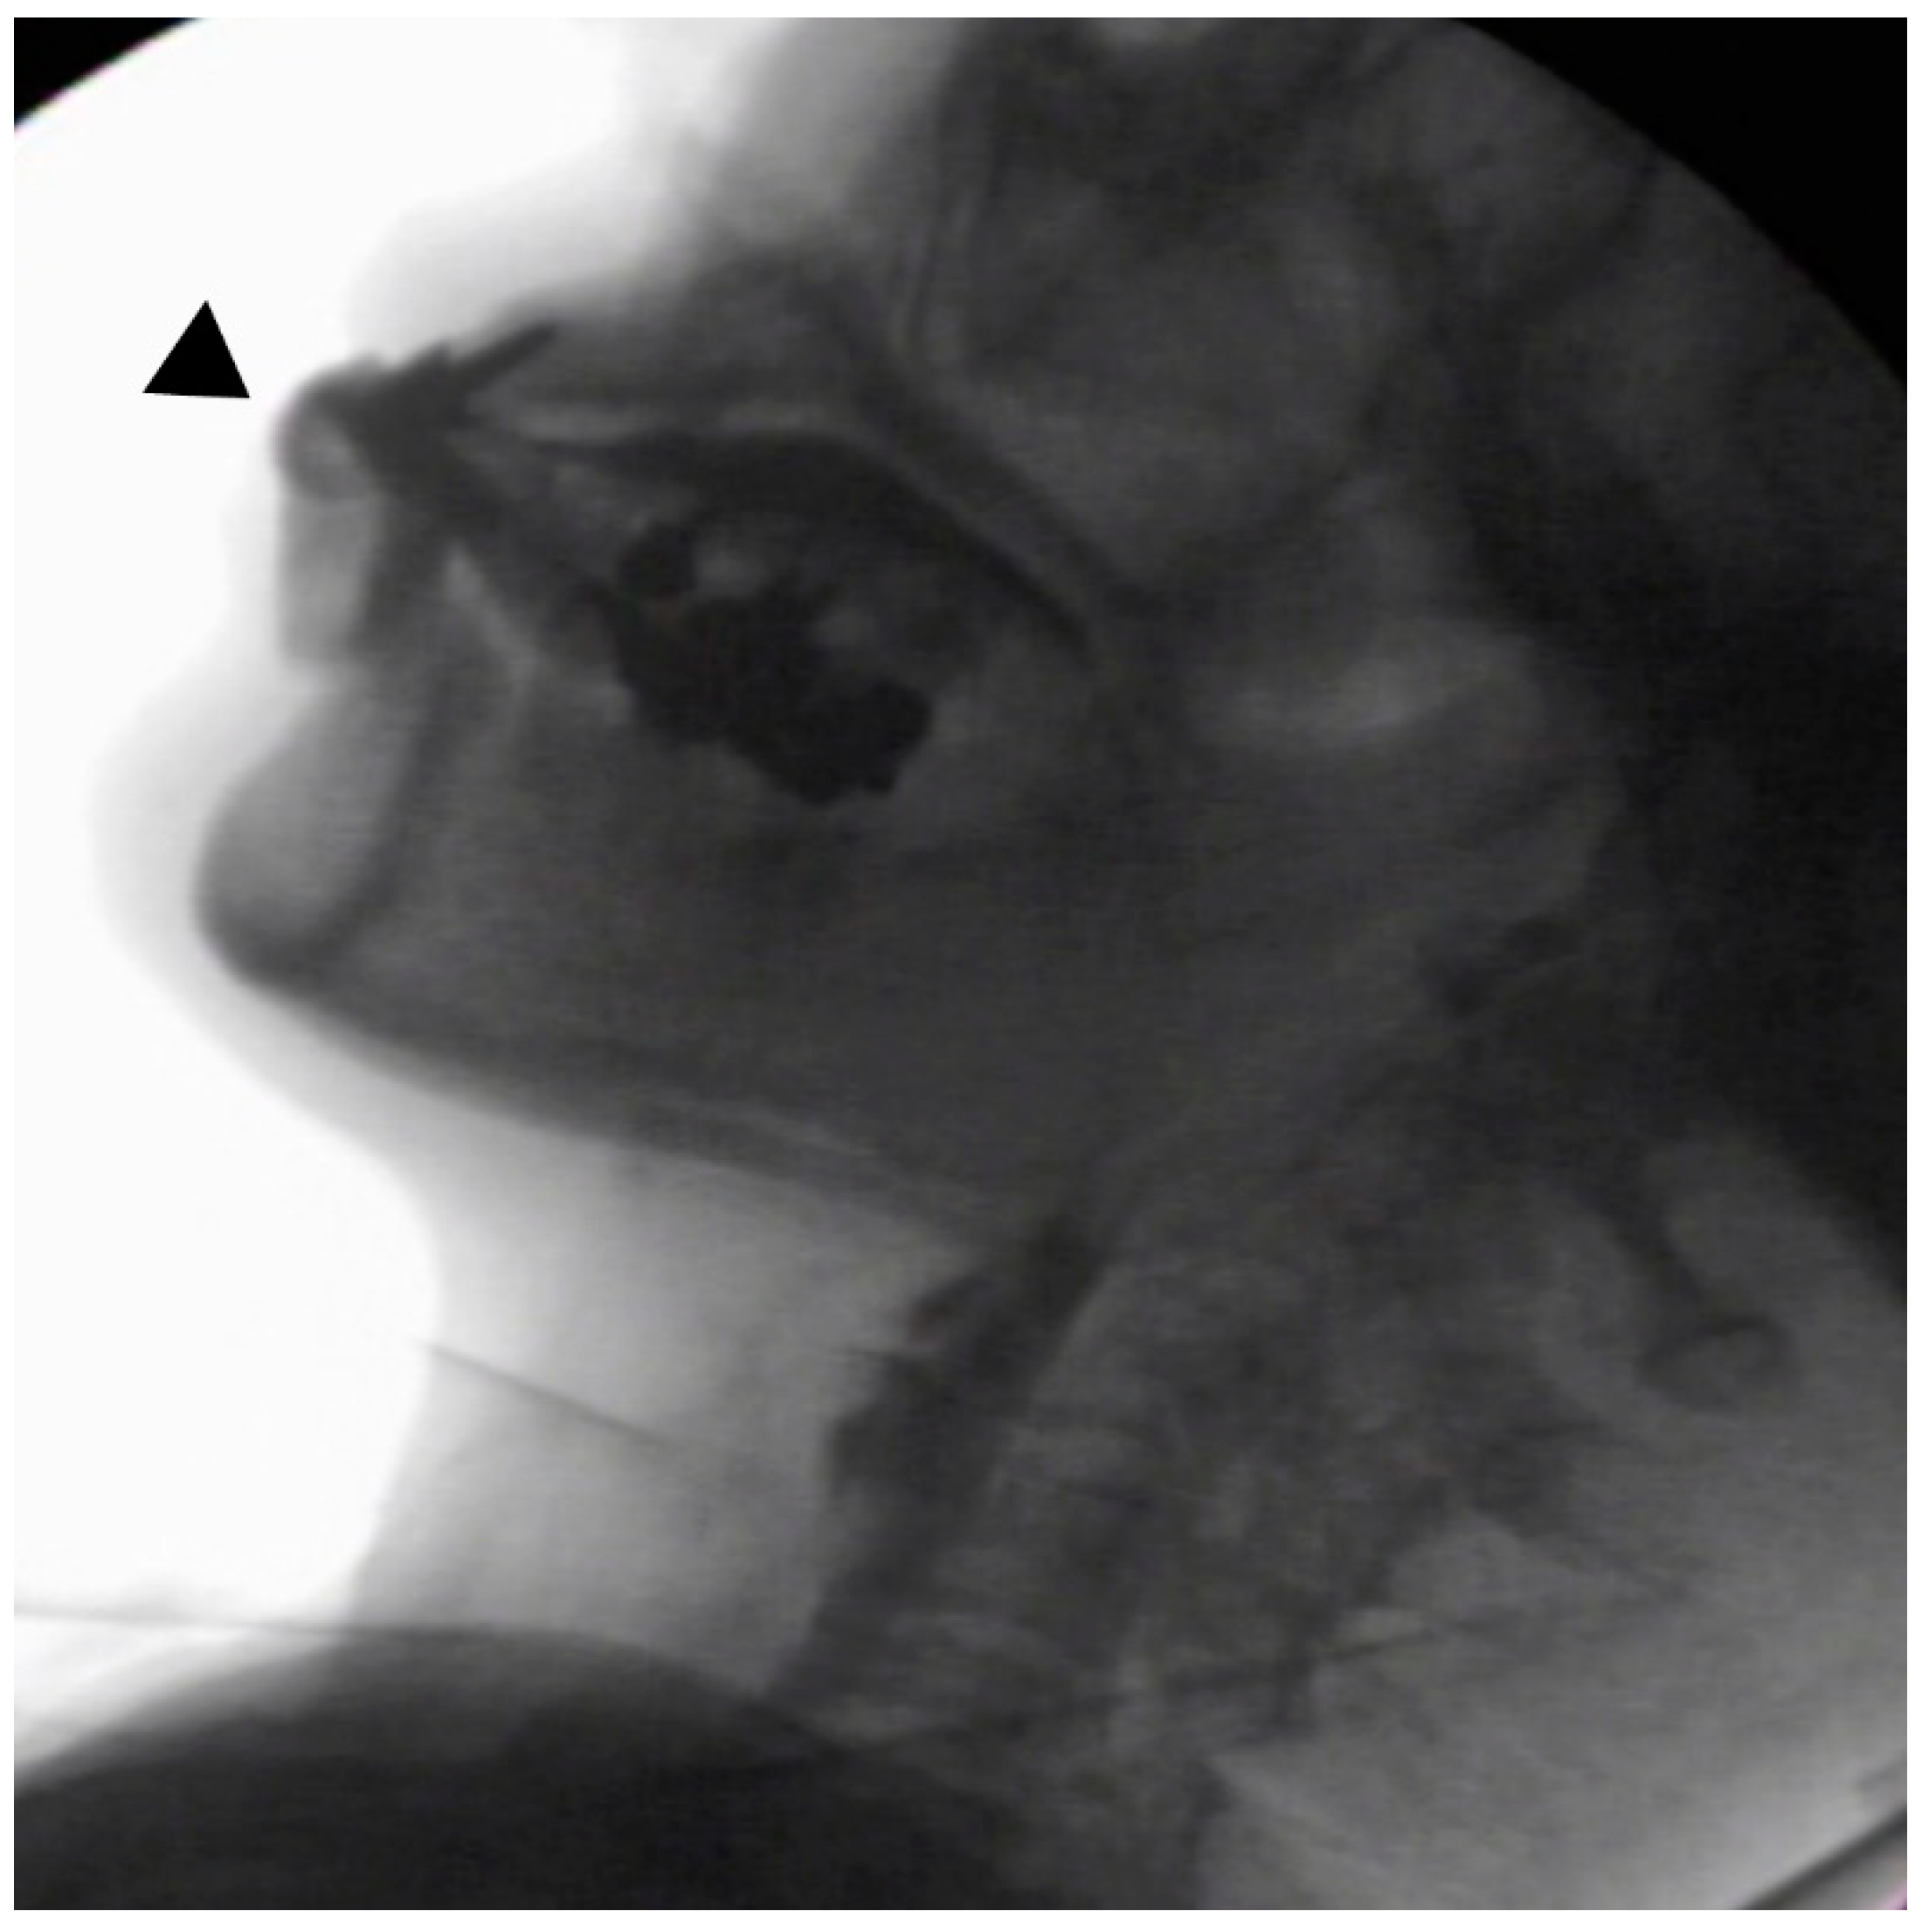

In the seated position, spoon-feeding was infeasible and bolus transport did not occur; furthermore, anterior–posterior tongue movement caused most of the food to dribble out of her mouth. After placing food on top of her tongue using a tube-fitted syringe, most still dribbled out of her mouth (Figure 1a); however, a proportion was transported into the pharynx (Figure 1b). Furthermore, after placing food at the back of her tongue with the patient reclined at 30°, a small amount still dribbled out of her mouth; however, the patient could swallow without aspiration (Figure 2). After increasing the amount placed in her mouth at one time to 7 mL, more food dribbled out of her mouth (Figure 3); additionally, there was a decreased amount transported to the pharynx. When 5 mL of a moderately thick paste was placed in her mouth, none of it dribbled out; however, slight silent aspiration was present (Figure 4). There were no particular issues observed due to peristalsis from the upper esophagus to the stomach.

Figure 1.

(a) Videofluoroscopic examination of swallowing (VF) with the patient sitting up. The test food was 5 mL of an extremely thick paste. Most of the food dribbled out of her mouth, with only a small amount being transported to the pharynx. (b) Maximum hyoid elevation upon deglutition.